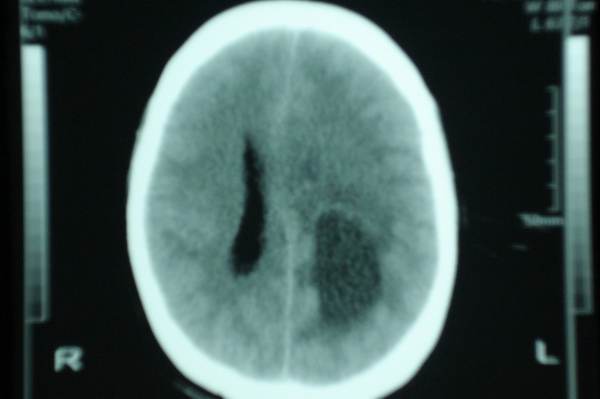

标题: CT11943:男,25,头痛伴癫痫发作数年.请会诊. [打印本页]

男,25,头痛伴癫痫发作数年.

左侧脑室局部受压闭塞,相应脑实质有等密度病变,顶叶区见均匀低密度病灶,外围见钙化有占位效应,胶质瘤可能,血管畸形不排除,建议强化或磁共振